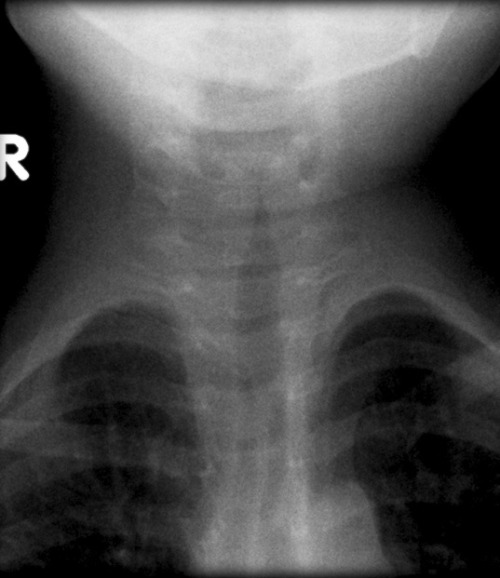

A 2-year-old girl is brought to an urgent care clinic by her guardian due to a harsh, barking cough and noticeable difficulty breathing that started overnight. Her guardian reports she's had a low-grade fever and mild nasal congestion for the past two days. On examination, she presents with inspiratory stridor and is using accessory muscles to breathe, though her oxygen saturation is stable at 94% on room air. A rapid point-of-care chest X-ray is performed, revealing characteristic subglottic narrowing. Considering the clinical presentation and radiographic findings, what is the most likely underlying etiology and the appropriate initial pharmacologic intervention?